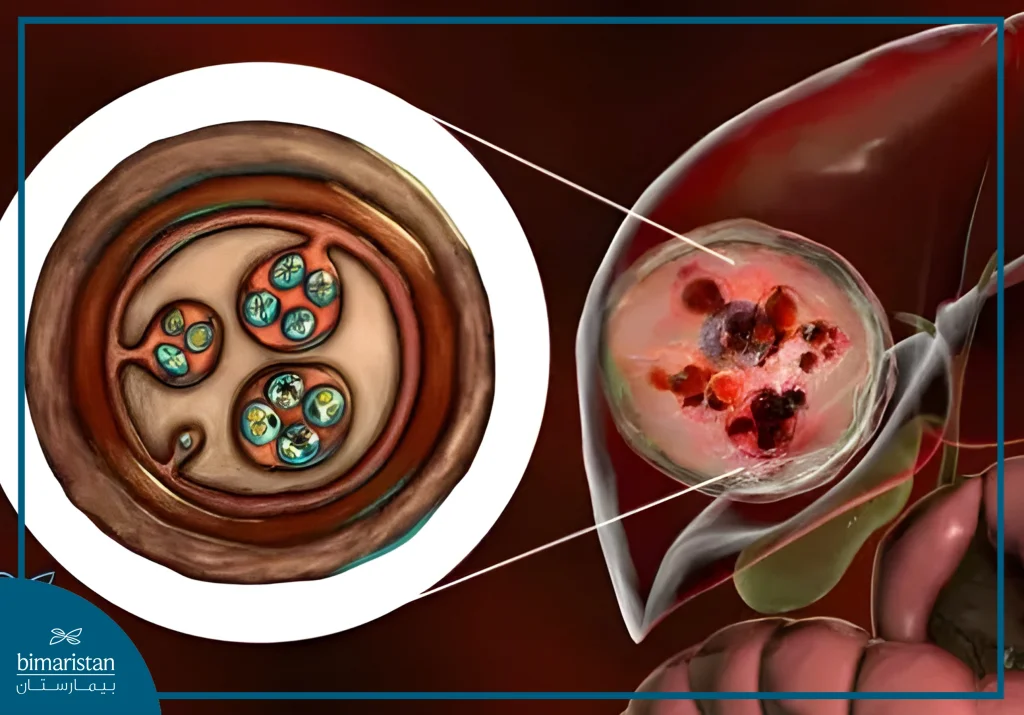

الكيس المائي (Hydatid cyst) هو آفة كيسية تنشأ نتيجة تطور الطور اليرقي لطفيلي المشوكة الحبيبية داخل جسم الإنسان. بعد ابتلاع البيوض تتحرر اليرقات في الأمعاء وتخترق الجدار المعوي لتصل عبر الدوران البابي إلى الكبد حيث تستقر وتشكل الكيسة.

يُعتبر الكبد هو العضو الأكثر إصابة بنسبة تقارب 60–70% تليه الرئتان بنسبة 20–30%. أما الإصابات في الطحال والكلى والدماغ والعظام والعضلات فهي أقل شيوعاً. المرض أكثر انتشاراً في المناطق الرعاية التي يشيع فيها الاحتكاك بين الكلاب والأغنام ويُعد الإنسان مضيف متوسط.

يؤدي انسكاب سائل الكيس المائي في الكبد الحاوي على الكيسات البنات والعناصر الطفيلية إلى ما يعرف بالانبثاث الثانوي، حيث تنزرع هذه العناصر في أماكن أخرى داخل التجويف البطني أو على الصفاق مما يسبب تشكل أكياس مائية جديدة متعددة ويزيد من تعقيد الحالة العلاجية واحتمال النكس مستقبلاً. لذلك يُعد التدبير الدقيق ومنع انسكاب محتويات الكيسة أثناء العلاج حجر الأساس في تقليل الاختلاطات وتحسين الإنذار.